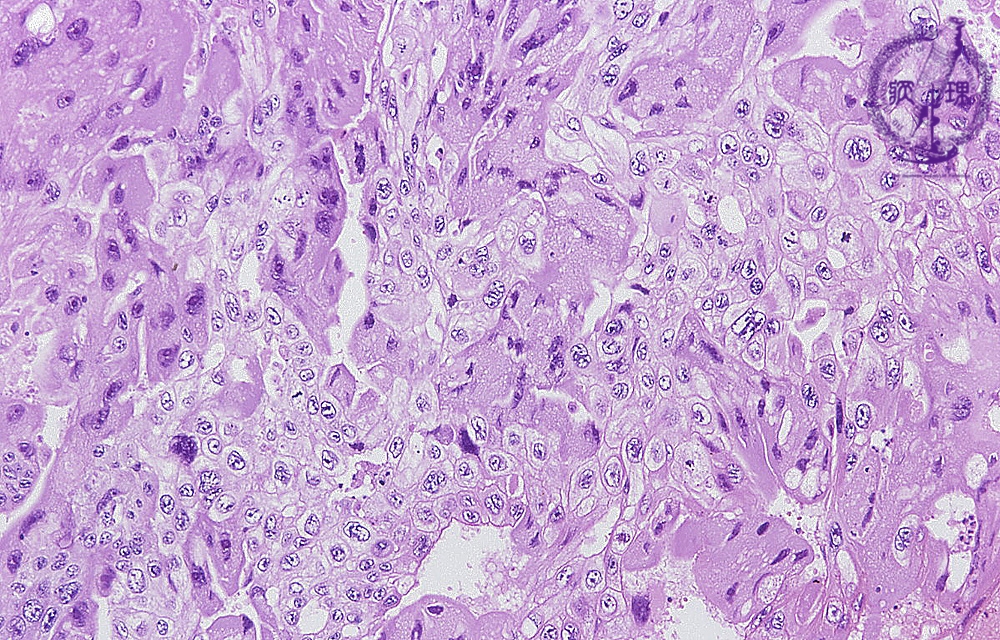

Histology (HE stain, low power):Multinucleated eosinophilic tumor cells mimicking syncytiotrophoblasts, (yellow dotted line) and tumor cells with clear cytoplasm mimicking cytotrophoblasts (blue dotted line) proliferate in sheet-like pattern. The former type of tumor cells produces and secretes human chorionic gonadotropin (h-CG) as identified by IHC (see below).